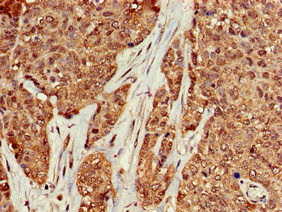

Immunohistochemistry of paraffin-embedded human colon cancer using CSB-PA13967A0Rb at dilution of 1:100